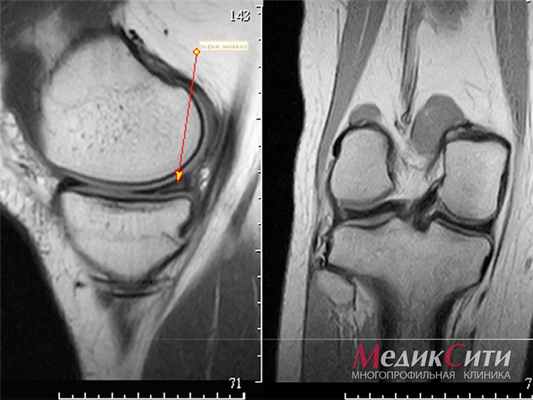

МРТ колена: норма